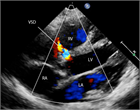

1. 心室中隔欠損は、欠損孔の部位により、膜性周囲部(perimembranous)、筋性部(muscular)、漏斗部または肺動脈弁下部(subarterial)に分類され、自然歴、手術適応が各々異なるため、部位診断は重要である。